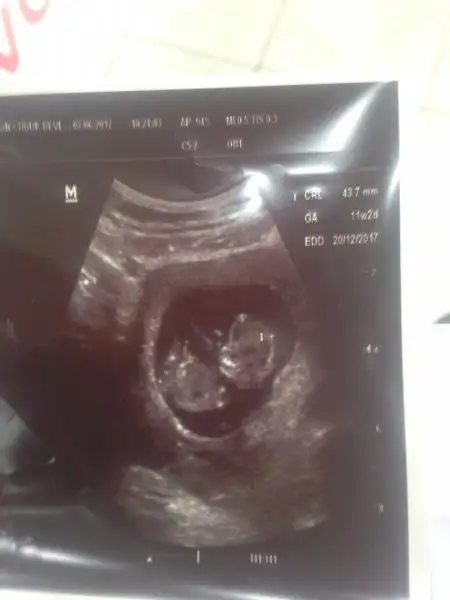

Himmm aslinda 19 unda alicam ikili test sonucunu ama birde parazit testi icin kan verdim oda 22 sinde cikicak oyizden hepsini bir alayim diye 22 sinde gidecem canim. Ben tahlilleri dogum 3vinde yaptiriyorumya kendi doktoruma muayen3 v3 kontrol amacli gidiyorum.Benimkide 20 sine senden önce öğrenecem.![]()